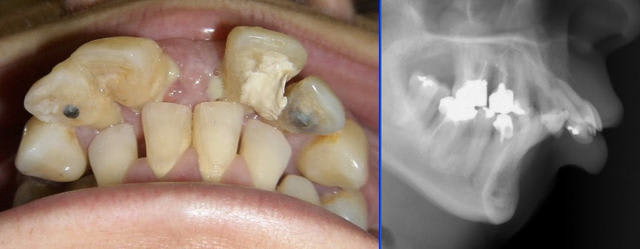

Gay-luron m’a demandé s’il y avait des mobilités.. En fait, la 22 n’a plus aucun support osseux, elle flotte littéralement. Al l’a bien vu, qui envisage de se faire moine tibétain…

Cette patiente a une classe II squelettique monumentale. Ce serait un cas chirurgical si la patiente le désirait.

Ses incisives « courent après le beefsteak », comme l’a si élégamment fait remarquer Tonio.

Elles sont tellement mobiles qu’une simple petite tape amicale sur sa joue risquerait d’en éjecter une ou deux..

Il y a des problèmes parodontaux. Signes inflammatoires et plus beaucoup (ou plus du tout pour la 22) de support osseux.

La première est sur la radio de profil : l’inclinaison des incisives inférieures est telle qu’elles viennent littéralement repousser les supérieures vers l’avant. Je remarque en passant que LaTrèsDouée (toujours elle !) est la seule à avoir évoqué le profil.

La seconde est que la 22 étant certes sortie de l’os, elle est toujours là depuis un certain temps. Mobile à l’extrême, mais toujours là...

Et si, dans ce cas, la situation extrême de ces dents était plutôt due aux phénomènes migratoires liés à l’occlusion des incisives inférieures qu’à une parodontite ? Les problèmes paro étant alors secondaires aux migrations ?

Un remise en place des dents permettrait alors d’espérer pouvoir les conserver..